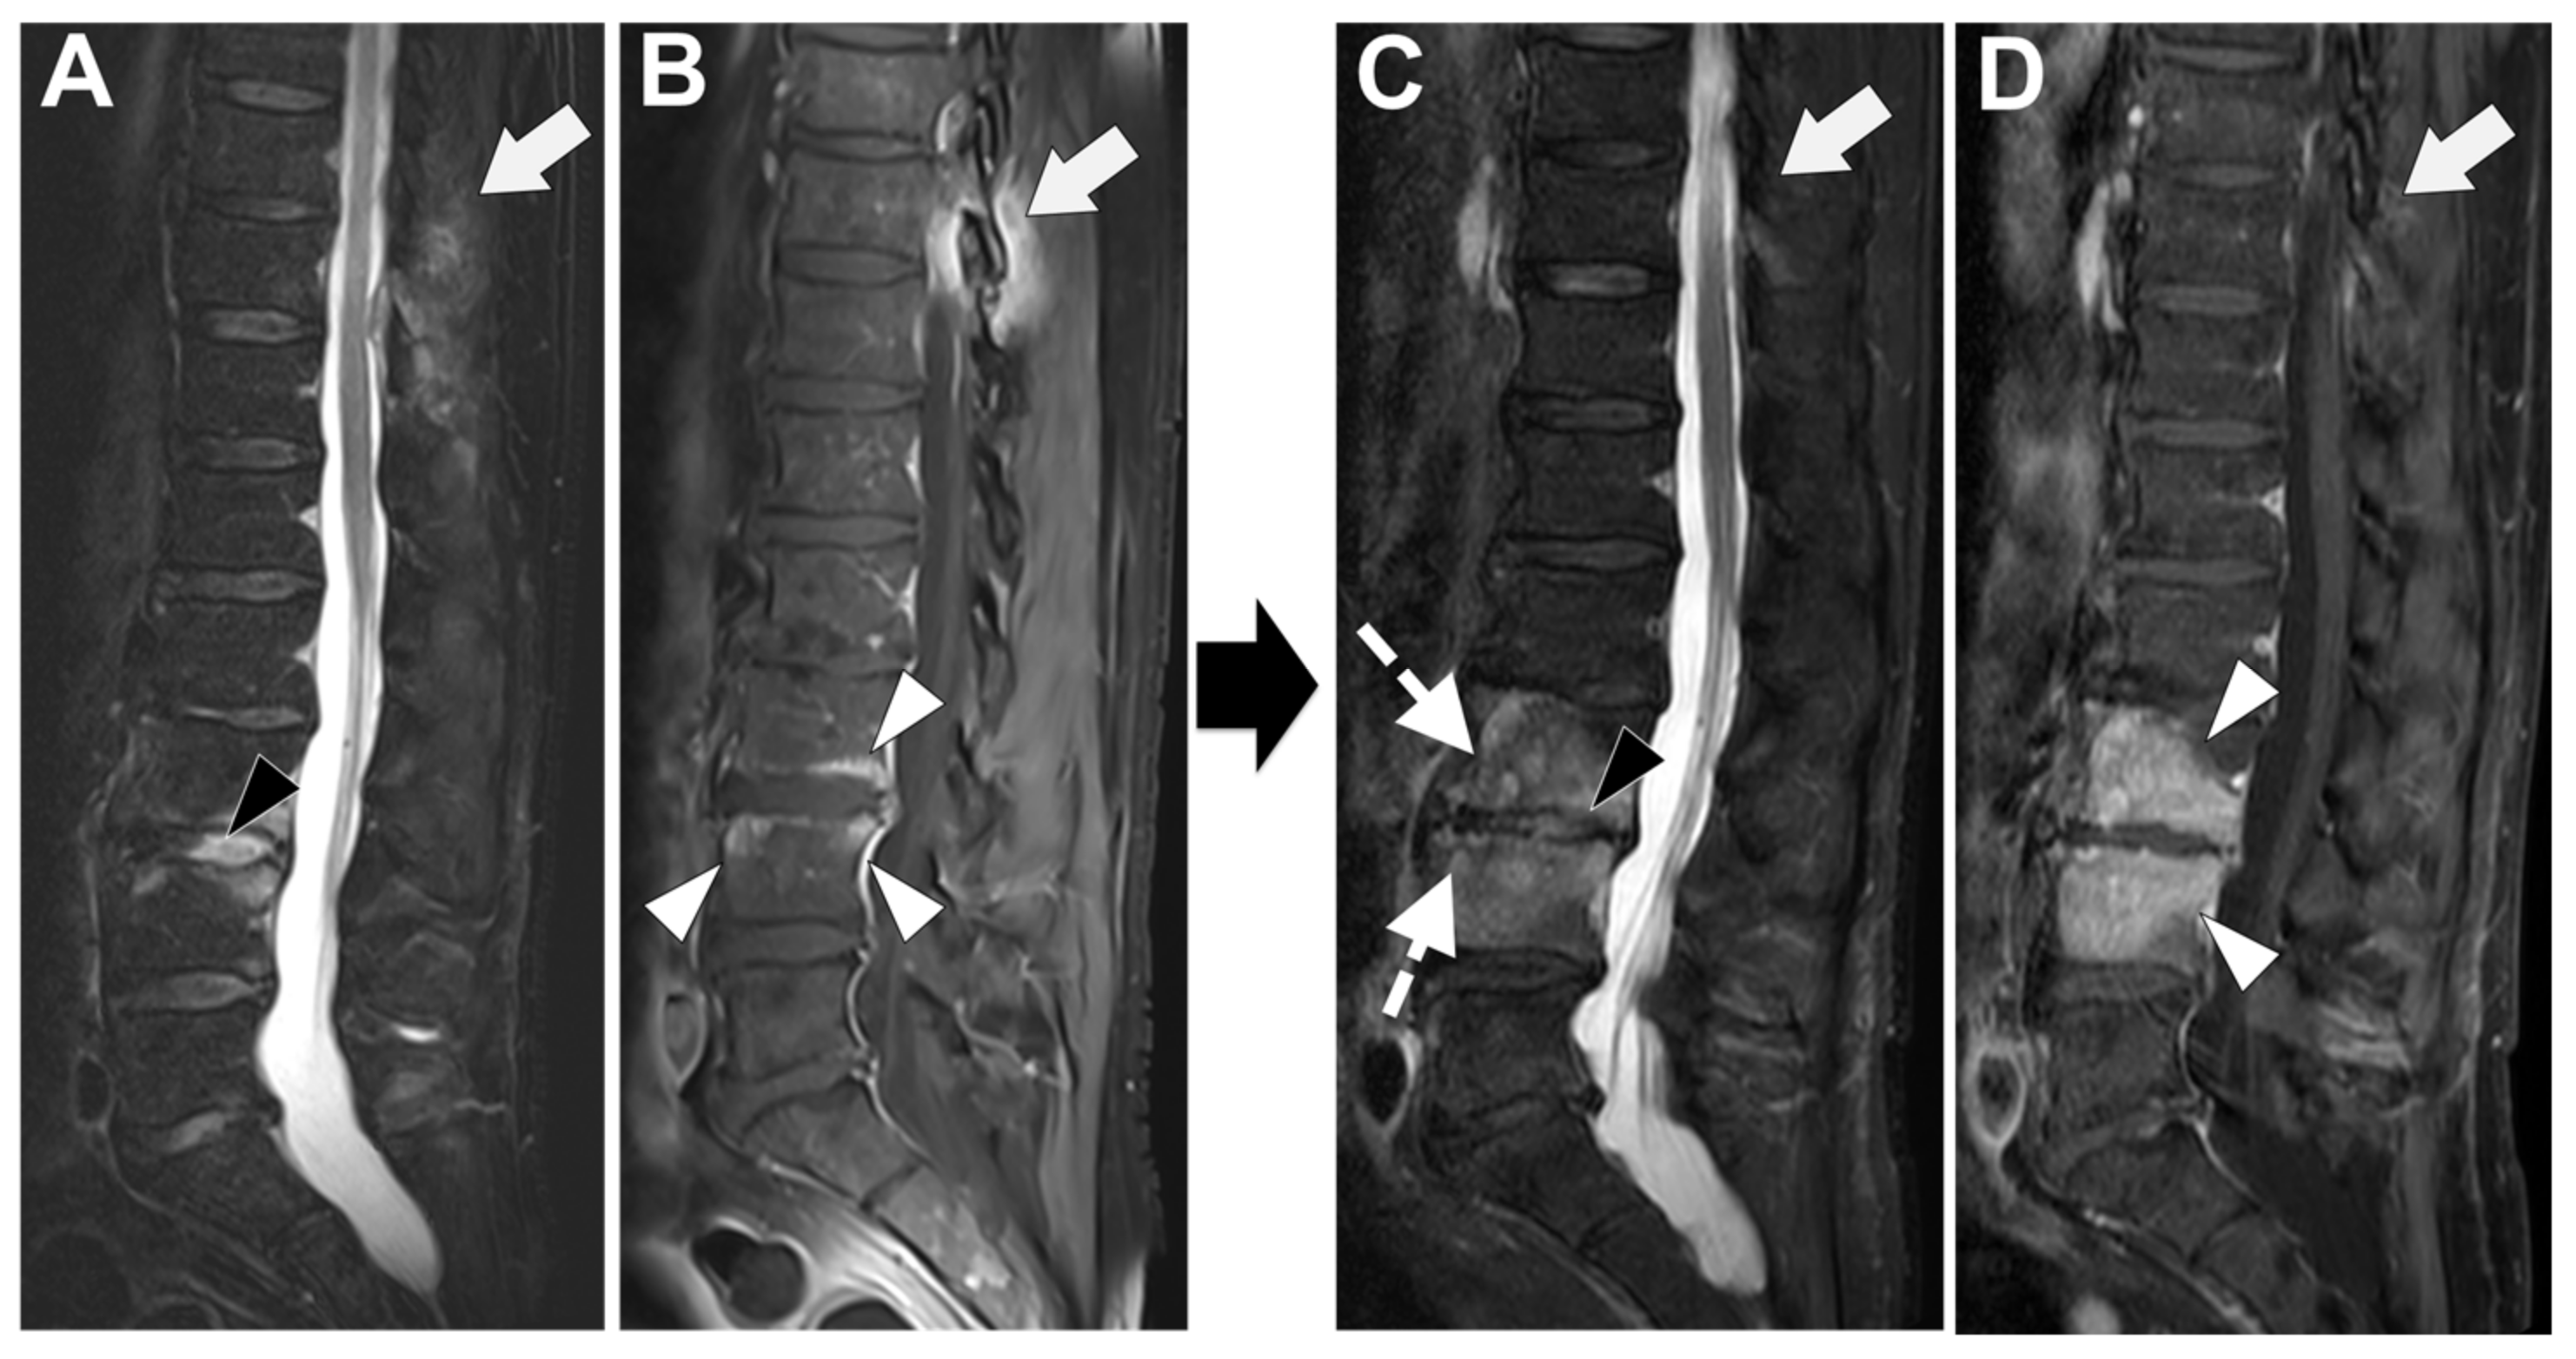

Figure 7. A 73-year-old male presented with a rapidly evolving lumbar pain and fever, with an inflammatory syndrome on blood samples. A first MRI was performed as infectious spondylodiscitis was suspected, which included (A) STIR T2-weighted imaging (WI) and (B) fat sat T1-WI after gadolinium chelates injection. It shows a high signal intensity (SI) of the L3-L4 disc while other disks are in lower signal (black arrowhead), as well as linear subchondral contrast enhancement (CE) of the L3-L4 endplates both linear and more pronounced at the upper anterior corner of the L4 vertebral body (white arrowheads). Moreover, the left T11-T12 facet joints displayed marked edema of the subchondral bone and surrounding tissues (white arrows). A control MRI with SITR T2-WI (C) and fat-suppressed CE-T1-WI (D) was performed one month later, demonstrating a marked narrowing of the L3-L4 disk (black arrowhead), erosions of the vertebral body (dashed white arrows), extensive edema in the L3 and L4 vertebral body (white arrowhead), a persisting arthritis involving the left T1-T12 facet joint. Bacillus cereus was found on the Bacterial analysis of the L3-L4 disk biopsy.

In Figure 7 an exemplificative case of PyS is presented.

Notably, pyogenic spondylodiscitis generally less frequently affects the posterior elements of the spine. Key findings with high sensitivity for diagnosing pyogenic spondylodiscitis include paraspinal or epidural inflammation, vertebral body T1 hypointensity, disc space T2 hyperintensity, and disc space enhancement [43].

Another typical feature of TbS is a heterogeneous signal of the vertebral body both on T1w, on fluid-sensitive, and on CE sequences [49,50,56].

Thereby concluding, the main features of PyS are the involvement of the lumbar spine, poor and ill-defined enhancement of the paravertebral tissues, diffuse/homogeneous vertebral contrast enhancement of vertebral bodies, low degree destruction of the vertebral bodies, high and homogeneous signal intensity of the vertebral bodies on T2-weighted images, disc signal change, and disc height loss [43,49,50,51,52,53,54,55,56]. Additionally, anterior subligamentous spreading and posterior spine structures are generally not involved [60].